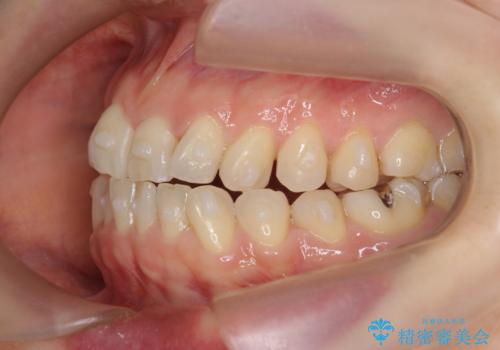

前歯の目立つガタつきをマウスピース矯正で治療

- 大きく傾いてしまった前歯のガタつきの改善を求めて来院されました。

前歯のガタつきをしっかりと取り、機能的・審美的に理想的な歯並びをマウスピース矯正で達成します。

強度のガタつきはマウスピース単体では並び切ることが難しいこともありますが、しっかりと装着していただいたことで良好な治療結果を得ることができました。